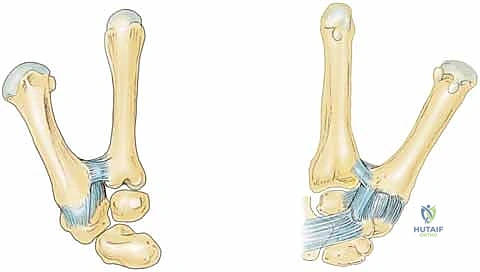

التشريح المعقد والدقيق لمفصل الإبهام القاعدي (CMC Joint)

لفهم سبب حدوث خشونة مفصل الإبهام وكيفية علاجها، من الضروري جدًا أن نُلقي نظرة تشريحية عميقة على هذا المفصل الفريد من نوعه في جسم الإنسان. مفصل الإبهام الرسغي المربعي (CMC) هو مفصل "سرجي الشكل" (Saddle Joint)، مما يعني أن الأسطح المفصلية للعظام تتداخل مع بعضها البعض مثل راكب يجلس على سرج حصان.

هذا التصميم التشريحي العبقري يمنح الإبهام نطاقًا واسعًا جدًا من الحركة في ثلاثة مستويات هندسية:

هذه المرونة الهائلة هي ما يجعل الإبهام أداة لا غنى عنها، ولكنها تأتي بتكلفة باهظة: قيود عظمية بسيطة للغاية. هذا يعني أن استقرار المفصل لا يعتمد على تداخل العظام العميق (مثل مفصل الورك)، بل يعتمد بشكل شبه كلي على شبكة الأربطة المحيطة به (Soft Tissue Restraints).

شبكة الأربطة المثبتة للإبهام

تُحيط بهذا المفصل شبكة معقدة وقوية من الأربطة. في الأدبيات الطبية، تم وصف ما يصل إلى 16 رباطًا مختلفًا في هذه المنطقة الصغيرة، منها 7 أربطة تُعتبر مثبتات أساسية لعظم المشط الأول (قاعدة الإبهام). تشمل هذه الأربطة الحيوية:

* الرباط المائل الأمامي السطحي والعميق (AOL): وهو الرباط الأهم والأكثر عرضة للإصابة والتراخي، وهو المسؤول الأول عن منع انزلاق المشطية.

* الرباط الكعبري الظهري (DRL): يوفر استقرارًا كبيرًا أثناء حركات الدوران.

* الرباط المائل الخلفي (POL).

* الرباط الجانبي الزندي (UCL).

* الأربطة بين المشطية (Intermetacarpal Ligaments).

الأربطة المتبقية تُثبت العظم المربعي (Trapezium) نفسه بعظام الرسغ الأخرى (مثل العظم القاربي وشبه المنحرف)، مما يوفر أساسًا صلبًا ومستقرًا لحركة الإبهام.